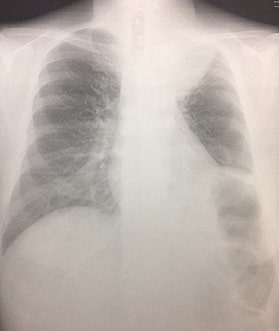

胸部X線検査では、肺野にノッチサイン(notch sign)やスペキュレーション(speculation)、胸膜嵌入像(きょうまくかんにゅうぞう)を伴う場合は、肺腺癌を疑います。

ノッチサインとは、肺がんの胸部エックス線で見られる凹凸像のことです。

スペキュレーションとは胸部X線上に見られる周囲の索状に見えるかげのことです。

胸膜嵌入像とは胸部X線で肺に胸膜が入り込んで肺の縁がめくれているように見える像のことです。